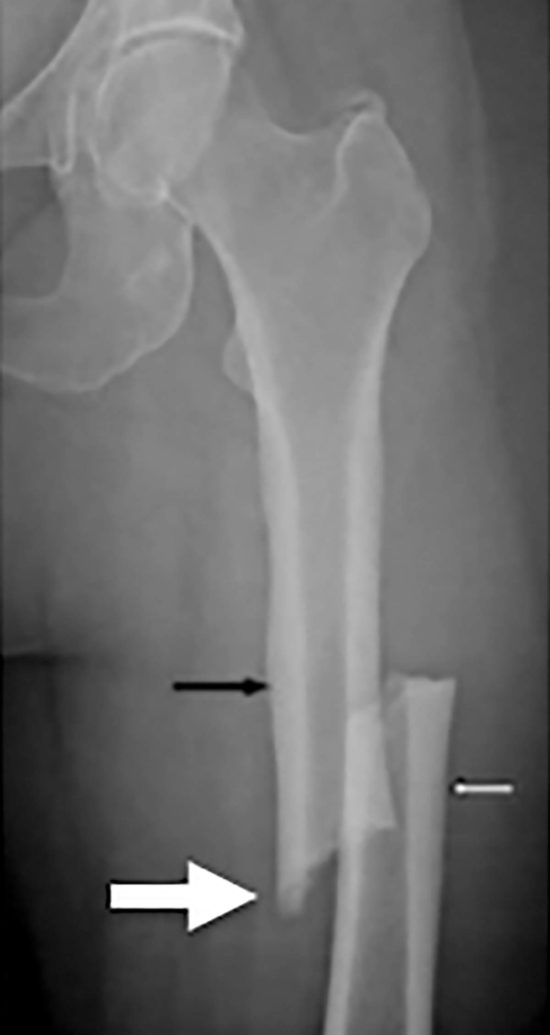

Not limited to management of osteoporosis, bisphosphonates have been used to treat a variety of pathologies ranging from Paget’s disease of bone to hypercalcemia of malignancy. Safety profiles for bisphosphonates show they are generally well-tolerated, but more recently there have been concerns about the long-term use of bisphosphonates. In 2005, Odvina et al first reported on a small number of patients who experienced primarily non-spinal fractures of the lower extremity and femur while on bisphosphonate therapy, with histological analysis showing markedly suppressed bone formation after prolonged bisphosphonate use. Subsequently, several authors have reported similar findings, all associated with chronic bisphosphonate use. In each case, the fractures were found to be secondary to low-energy mechanisms, presented with prodromal thigh pain, and demonstrating a prominent femoral cortex medial spike radiographically (Figure 1). Bilateral AFFs have been reported in up to 48% of cases. Cortical thickening near the fracture site and delayed union after surgical repair have also been reported.

Figure 1. Representative atypical femur fracture radiograph. A 65-year-old female patient was taking bisphosphonates for 6 years, with 6 months of progressive prodromal thigh pain. She had seen an orthopedic surgeon 1 month prior to the fracture with pelvic X-rays showing no evidence of significant osteoarthritis at the time. Note the periosteal thickening of the lateral cortices (black and white arrows), noncomminuted transverse fracture, and the medial cortical spike (big arrow) that are typically seen in atypical femur fractures.